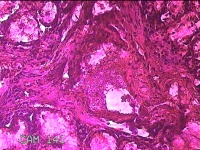

左侧鼻腔新生物

性别

女

年龄

43岁

临床诊断

1.慢性鼻窦炎 2.鼻息肉 3.鼻中隔偏曲 4.鼻腔粘连 5.变应性鼻炎

一般病史

鼻塞、脓涕3月余。’

标本名称

大体所见

灰白暗红色不规则肿物1.3x0.3x0.2cm一个,表面糜烂,内有少许骨质。